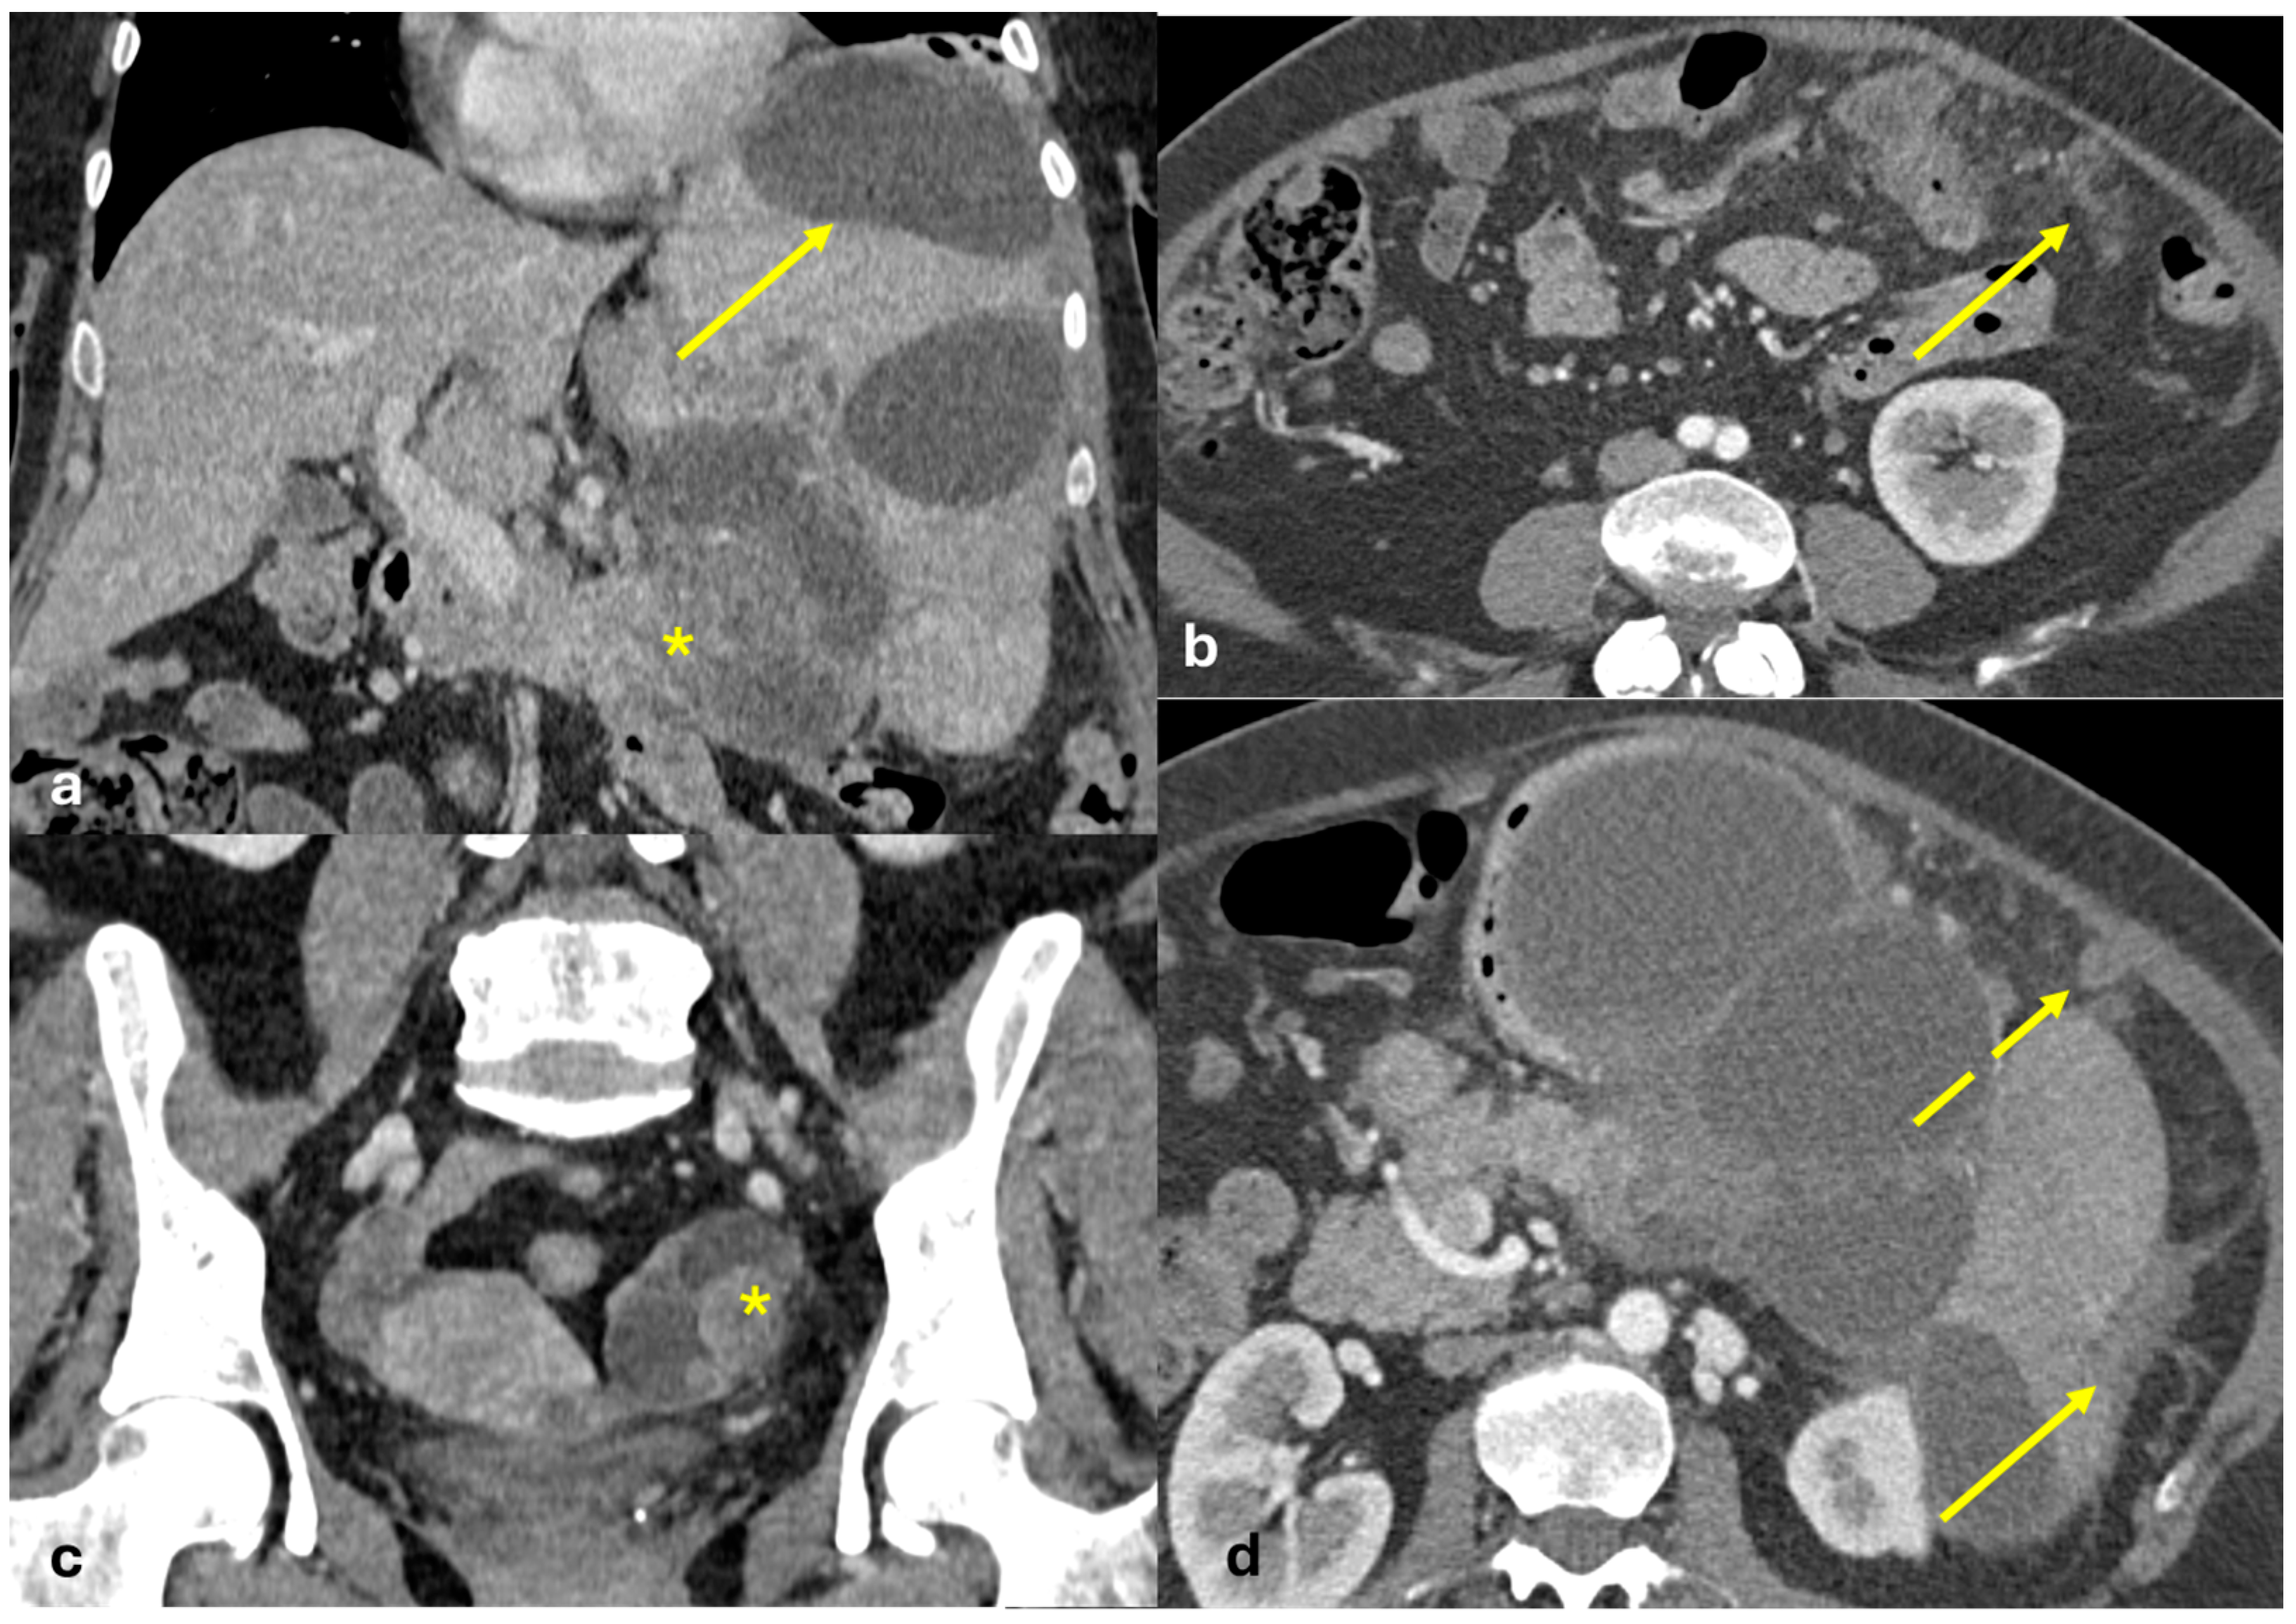

- Nodular pattern: nodules with a diameter > 5 mm (Figure 2a);

- “Omental cake”: nodular thickening of the omentum (Figure 2b);